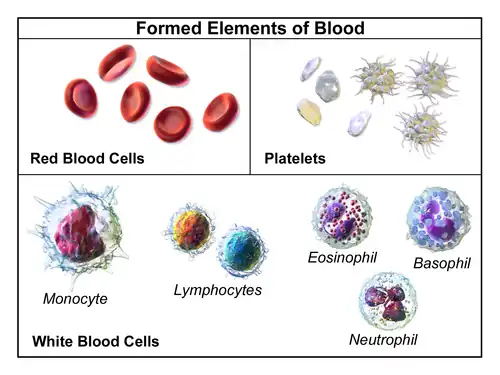

Illustration depicting formed elements of blood

Illustration depicting formed elements of blood -

Cells

One microliter of blood contains:

- 4.7 to 6.1 million (male), 4.2 to 5.4 million (female) erythrocytes:[13] Red blood cells contain the blood's hemoglobin and distribute oxygen. Mature red blood cells lack a nucleus and organelles in mammals. The red blood cells (together with endothelial vessel cells and other cells) are also marked by glycoproteins that define the different blood types. The proportion of blood occupied by red blood cells is referred to as the hematocrit, and is normally about 45%. The combined surface area of all red blood cells of the human body would be roughly 2,000 times as great as the body's exterior surface.[14]

- 4,000–11,000 leukocytes:[15] White blood cells are part of the body's immune system; they destroy and remove old or aberrant cells and cellular debris, as well as attack infectious agents (pathogens) and foreign substances. The cancer of leukocytes is called leukemia.

- 200,000–500,000 thrombocytes:[15] Also called platelets, they take part in blood clotting (coagulation). Fibrin from the coagulation cascade creates a mesh over the platelet plug.